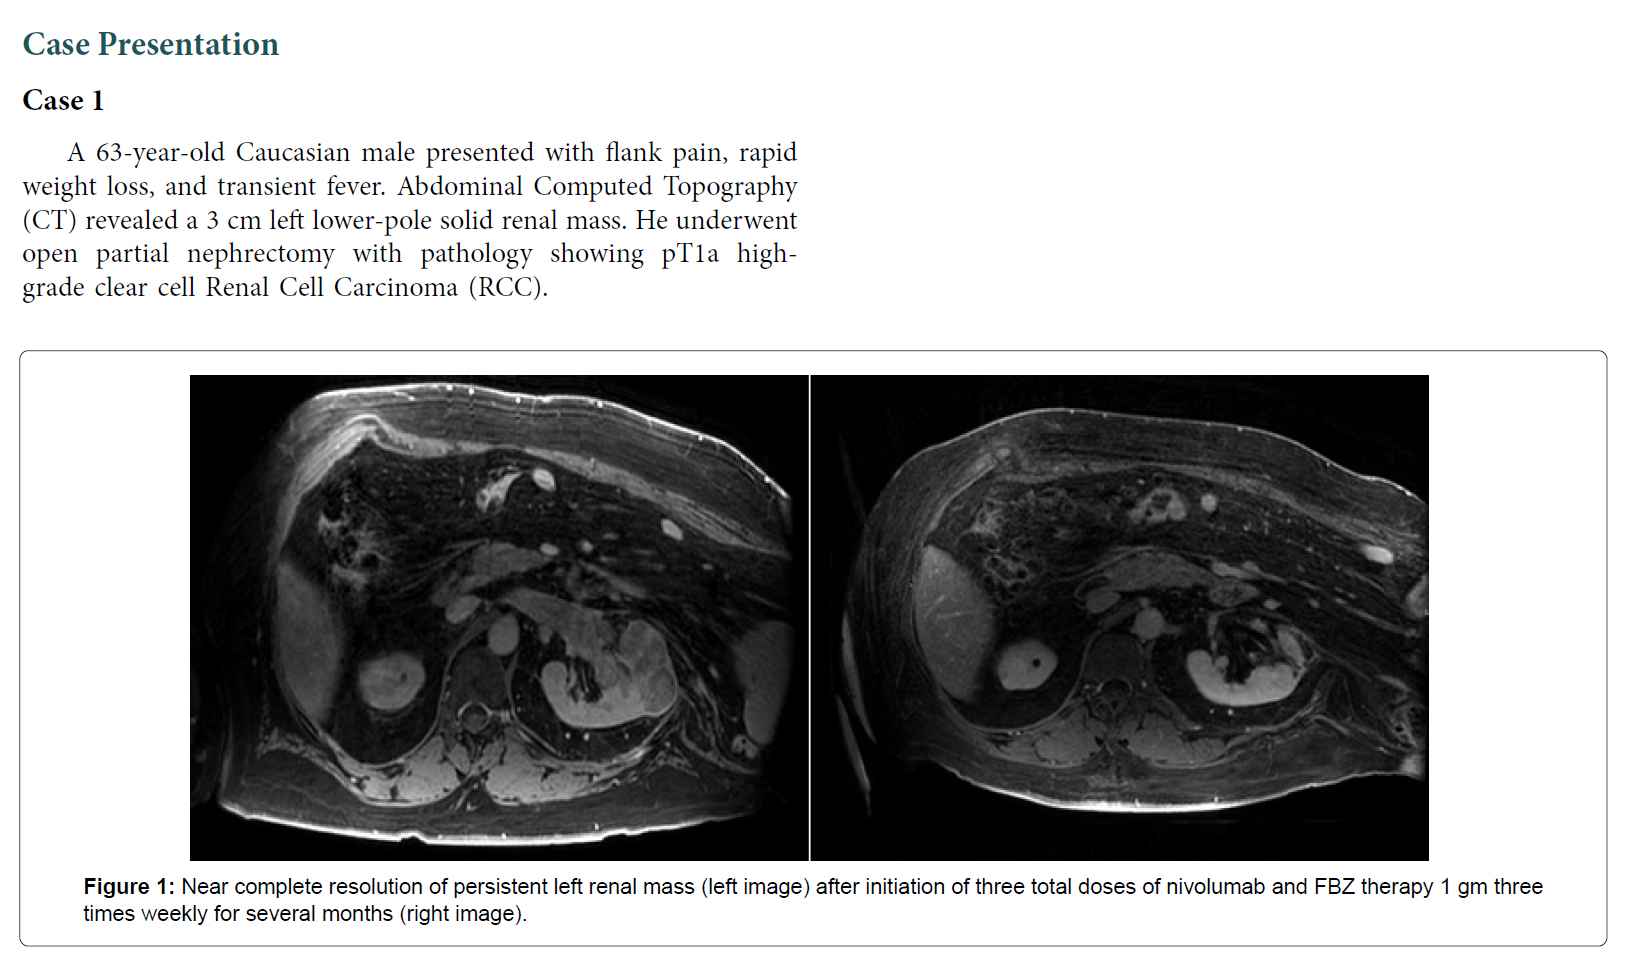

病例 1:63 岁男性,患有 4 期肾细胞癌(透明细胞),肿块 5.3 厘米,并转移到胰腺和骨骼,3 次化疗失败。每周服用 3 次 1000 毫克芬苯达唑后,他病情得到缓解,肿瘤大幅缩小。

病例陈述案例 1 ...... ...... 讨论总之,我们有三名患有不同原发性泌尿生殖系统肿瘤的患者在接受 FBZ 治疗后表现出完全缓解。这提出了一个问题:FBZ 作为抗癌剂的效果如何,值得进一步研究。据我们所知,目前还没有类似的病例系列报道。 FBZ 属于一类微管不稳定剂,统称为苯并咪唑。破坏微管聚合以诱导有丝分裂停滞和促进细胞凋亡的能力是长春花生物碱的共同特征。FBZ 抗肿瘤特性的拟议机制包括抑制蛋白酶体活性、p53 活化、通过破坏微管蛋白产生细胞毒性以及下调对癌细胞存活至关重要的糖酵解酶 [ 1,4 ] 。其他苯并咪唑(如阿苯达唑)通过影响对 VEGF 表达和糖酵解的某些方面至关重要的 HIF- 1 -alpha 通路而具有抗肿瘤特性 [ 5 ]。这类药物发挥作用的机制多种多样,可能有助于通过靶向癌细胞存活的多种途径来限制耐药癌细胞系的增殖。 FBZ 已被安全地用作各种动物的抗寄生虫药,并可重新用于治疗人类恶性肿瘤。几种苯并咪唑类药物已显示出在人类身上重新利用的前景。一个例子是帕苯达唑,它已证明作为吉西他滨的补充疗法对胰腺癌患者有潜在疗效 [ 6 ]。病例报告显示,甲苯咪唑对转移性肾上腺皮质癌和转移性结肠癌患者有效,且副作用少 [ 7,8 ]。动物研究还显示甲苯咪唑和氟苯咪唑分别对多形性胶质母细胞瘤和血液系统恶性肿瘤有效 [ 9,10 ]。鉴于对多种恶性肿瘤具有高耐受性和适用性的证据,这值得进一步研究 FBZ 和其他苯并咪唑作为安全的化疗选择。 先前的研究表明,癌症对免疫检查点抑制剂(如 nivolumab)有反应,可作为 mRCC 的三线药物 [ 11 ]。治疗时间通常要长得多,中位治疗时间为 6 个月,三线治疗的总体反应率为 24%。我们的第一位 mRCC 患者可能仅使用 nivolumab 而不使用 FBZ 就获得了显著反应。然而,考虑到仅 1 个月的免疫检查点抑制剂治疗就获得了完全的放射学反应,FBZ 似乎也在诱导缓解方面发挥了重要作用。我们的患者在仅使用 FBZ 近一年且未进一步进行免疫检查点抑制剂治疗的情况下仍保持了长期缓解,这一事实支持了这一观点。 结论目前数据有限,关于 FBZ 抗癌特性的已发表研究很少。其他苯并咪唑类药物的研究范围更广,可以利用这些知识来帮助指导未来的 FBZ 研究,并评估此类药物的疗效,无论是作为单一药物还是联合治疗。鉴于 FBZ 的潜在益处以及似乎有限的毒性,有必要进行进一步研究,以评估这种药物可能有益的临床环境,并将其重新用于患有进行性生殖泌尿系统恶性肿瘤的患者,甚至可能用于其他恶性肿瘤。